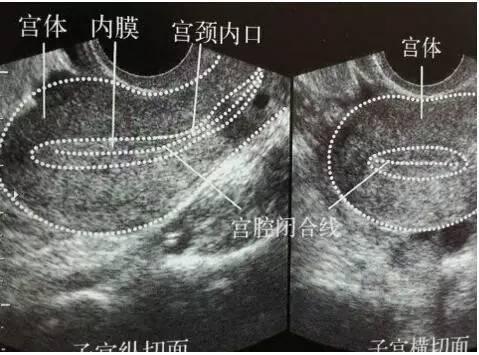

2. B超

影像显示子宫呈单角形,可见一侧卵巢。